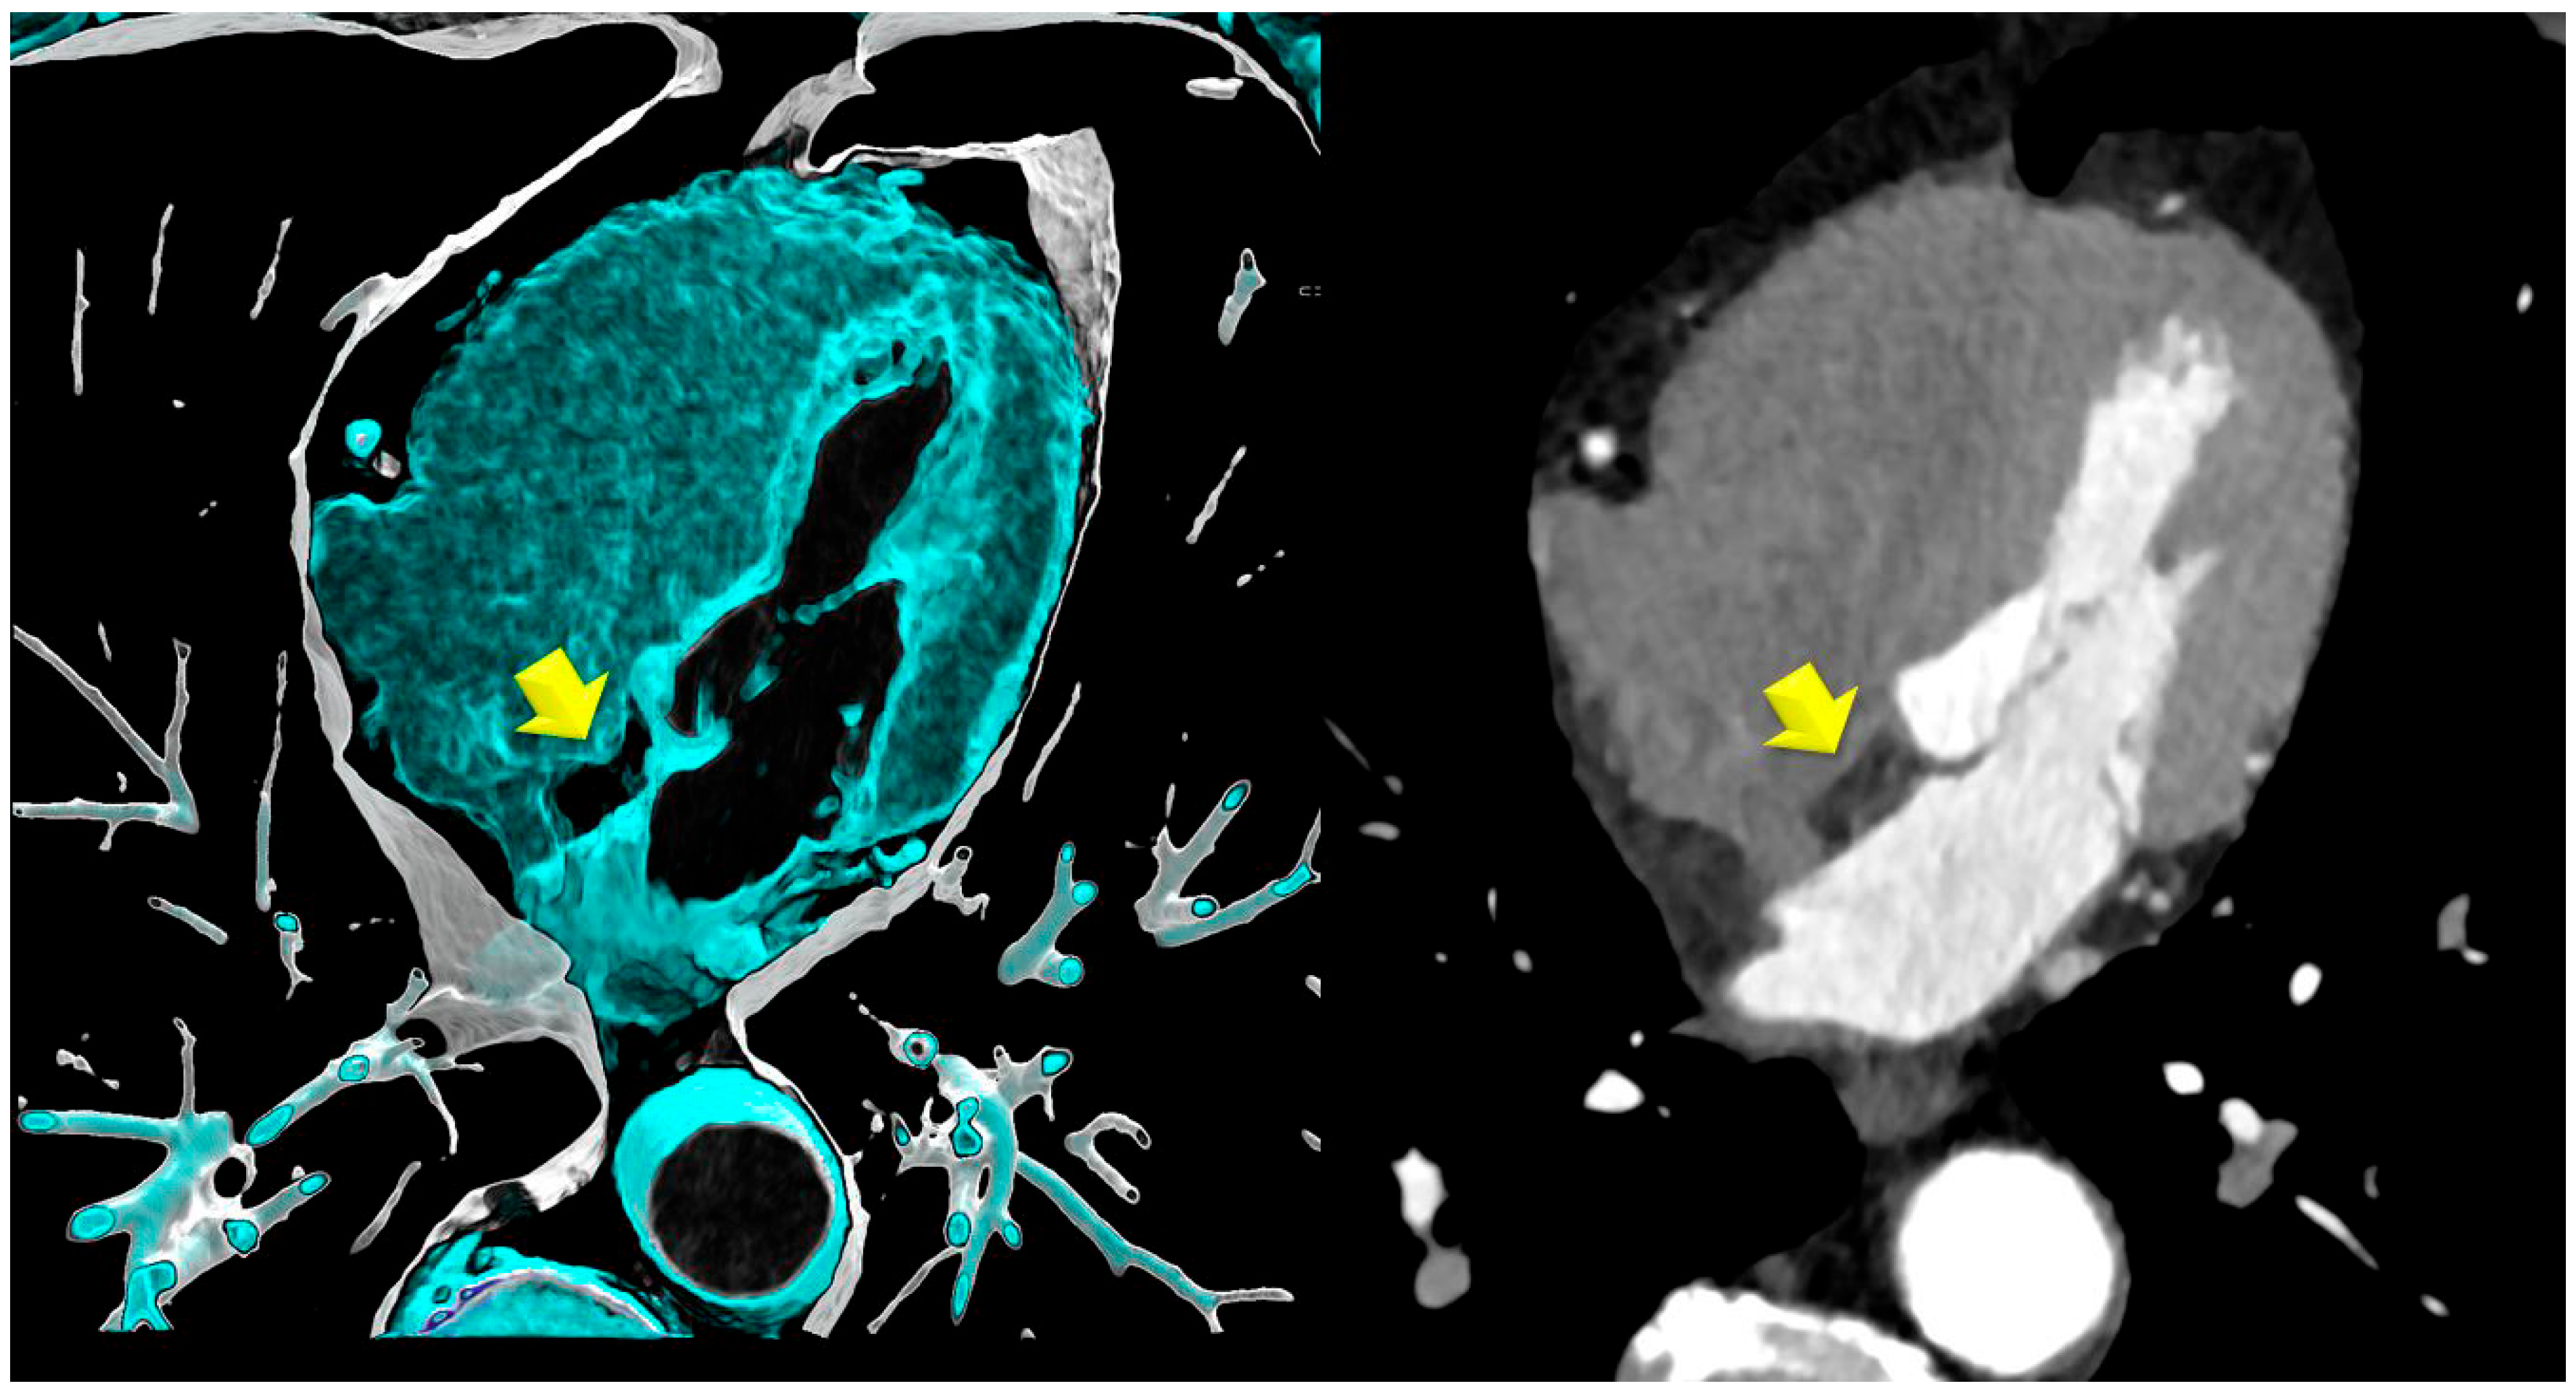

- Lipomatous hypertrophy of the interatrial septum (LHIS): This is defined as a mass-like lipomatous tissue infiltration of the entire interatrial septum from cranial to caudal, sparring the fossa ovalis, with a “dumb-bell” configuration with >than 5 mm width.The maximal width was identified on axial images and measured with a digital caliper. The maximal length was defined as the distance from the anterior to the posterior borders.